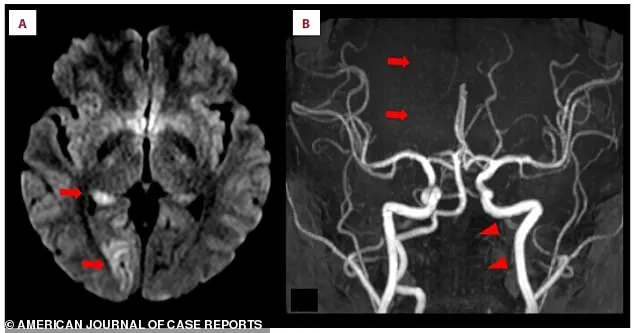

Medical imaging revealed the full extent of the crisis.

An MRI scan showed bright white spots in the right occipital lobe, indicative of acute ischemic stroke.

Closer inspection of the posterior cerebral artery, which supplies blood to the brain’s visual centers, revealed a missing section—a blockage that had severed the flow of oxygen-rich blood.

The scans also pointed to a critical issue in the left vertebral artery, a key blood vessel in the neck.

It appeared faint and thin, suggesting chronic narrowing that had likely gone unnoticed until this emergency.

The final piece of the puzzle was a crescent-shaped blood clot embedded in the artery’s wall, the direct cause of the blockage.

This clot had traveled from a distant site, lodging itself in a vulnerable artery and triggering the stroke.